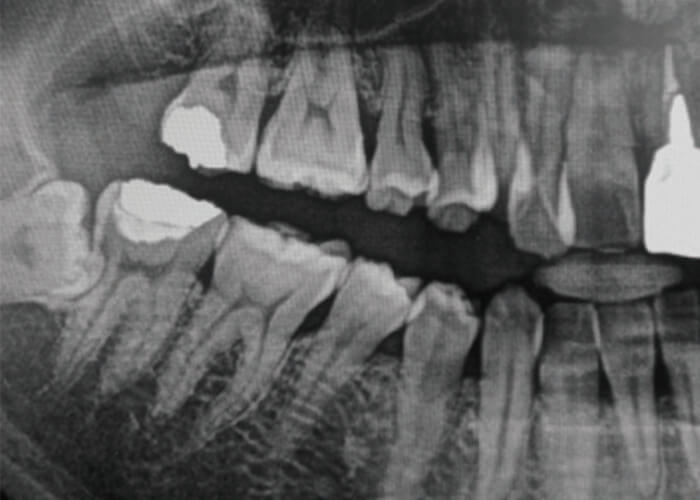

一般的には、症状がどのように始まり、どのように変化したかをお聞きし、顎関節や筋肉、口の中を診査し、必要に応じてエックス線撮影やCTによって骨の異常の有無を調べ、骨以外の関節構造や筋肉の問題についてはMRIによって調べる場合もあります。

顎関節症で出現する痛みや口の開けにくさは、親知らずの炎症や他の病気でも出ることがある症状なので、顎関節症であることを診断するためには、他の病気によって出てきている症状ではないことを確認する必要があるのです。

最も多いのは関節内にある関節円板(図1)というクッションが前方にずれることで起きる「カクンカクン」という音が出る状態(図2)、あるいはずれがもっと大きくなることで大きな口が開けられなくなる状態です(図3)。

特に口が大きく開かなくなると、口を開けたり食品をかもうとするときに痛みが出ます。この2つの状態で来院される方が全体の60%ほどになります。